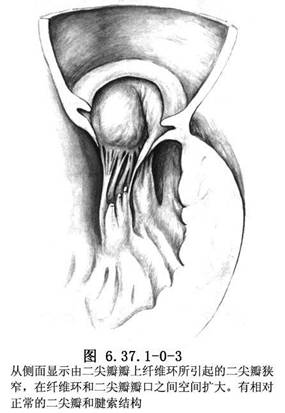

⑤瓣上纤维环:二尖瓣本身正常,而在其左心房侧紧贴瓣环有一环状纤维隔膜,中间有一孔洞形成狭窄。此畸形与三房心的区别在于后者隔膜靠近肺静脉,位左心耳上方(图6.37.1-0-2,6.37.1-0-3)。